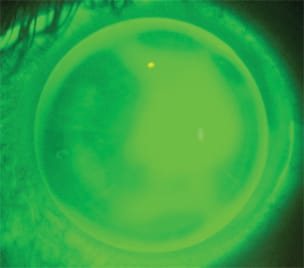

Upon dispensing, the patient's custom lens centered well with a slight temporal displacement (Figure 6), which followed the lateral asymmetry of the baseline cornea. The lens shared its bearing over a broad circumference of the peripheral cornea, which resulted in an acceptable fit and comfort. Although the visual acuity could not be improved beyond 20/25, the patient reported that the quality and stability of vision was noticeably improved compared with glasses and previous soft lens wear.

Figure 6. Custom ordered BE Retainer lens designed for orthokeratology but adapted for the post-surgical oblate cornea.